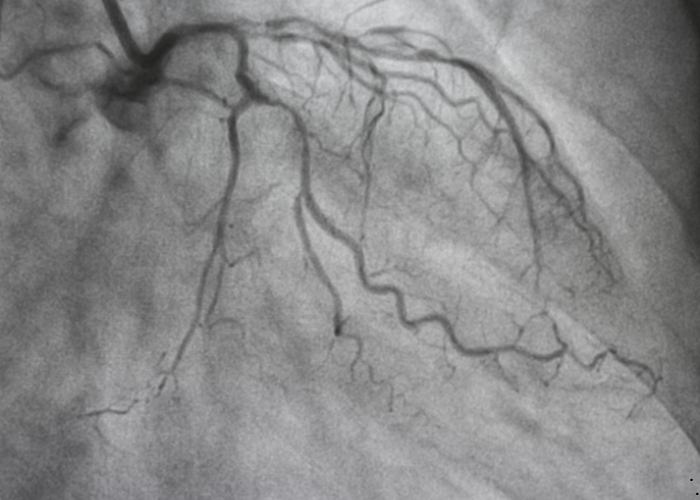

It is a specialized test that shows the inside of your heart’s blood vessels.

A contrast dye is injected, and X-rays are taken to detect blockages or narrowing.

Then, a contrast dye is injected to make the blood flow visible on X-ray.

The images show how well blood is reaching the heart muscle.

It’s considered the gold standard for diagnosing coronary artery disease.